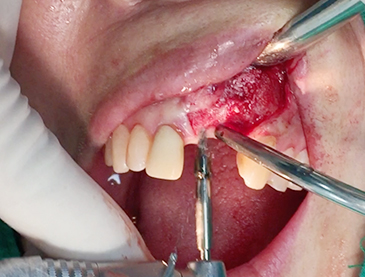

Partial edentulous clinical cases